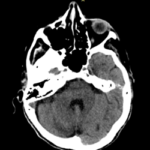

Las calcificaciones del sistema ventricular constituyen un error clásico y se confunden con hemorragias o masas.

Fig. 3.

Dentro de las astas posteriores de los ventrículos laterales a veces nos encontramos con xantogranulomas de los plexos coroideos. Debemos tener presente que estos se componen por quistes neuroepiteliales sin valor patológico.

Cavidades del septum. El septum es un fino tabique formado por dos láminas gliales ubicadas entre el cuerpo calloso en dirección cefálica y el trígono caudalmente. Existen tres variantes: el cavum pellucidum, cavum vergae y cavum interpositum.

Fig. 4.